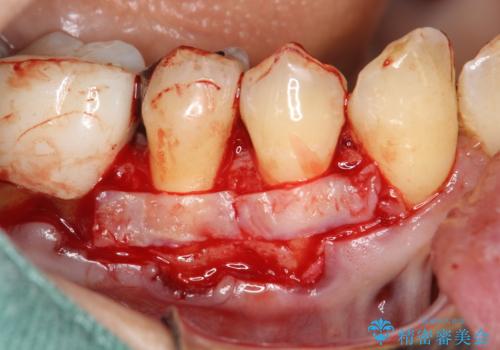

今回のケースでは小臼歯2本分の幅に渡って丈夫な歯肉を確保させるため、オペのデザイン上、横に幅広く均一な結合組織を採取する必要がありました。そのため、トラップドア方式で内部の組織をえぐって採取する術式は使わず、上顎歯肉の表層から結合組織部までを含む部分までを遊離歯肉採取の要領でやや深めに採取し、表層部分をトリミングする事で均一な厚みの結合組織を採取しました。この術式の利点として、上顎の歯肉に過度に深い侵襲を与える事がないため、組織採取部の術後の治癒が非常に早く、術後の不快症状も少なくて済む事が挙げられます。

術後3ヶ月にて意図した通りに丈夫な歯肉の幅が増大し、厚みも十分に確保できました。

これで歯肉が下がることを気にせずしっかりとブラッシングしていただく事が可能になりました。